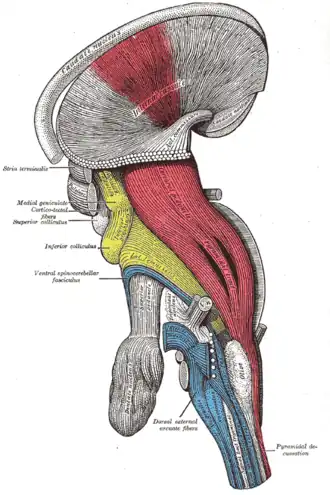

Sketch of the brainstem, with the pyramidal tract visible in red, and pyramidal decussation labeled at lower right.

Sketch of the brainstem, with the pyramidal tract visible in red, and pyramidal decussation labeled at lower right. -